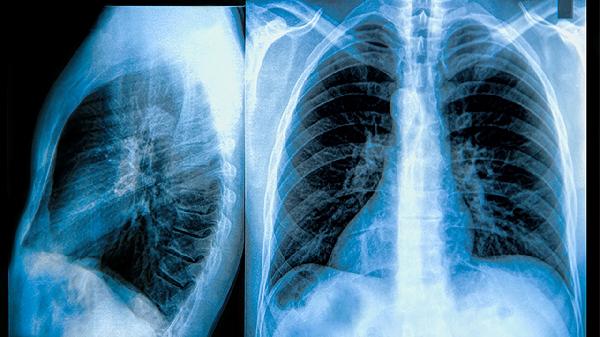

治疗中分化癌的方法包括手术、放疗和化疗。手术是主要的治疗手段,通过切除肿瘤组织,减少癌细胞的扩散。放疗利用高能射线杀死癌细胞,适用于无法手术或术后辅助治疗。化疗通过药物抑制癌细胞的增殖和扩散,常用于晚期或转移性癌症。靶向治疗和免疫治疗也逐渐成为中分化癌的重要治疗手段。